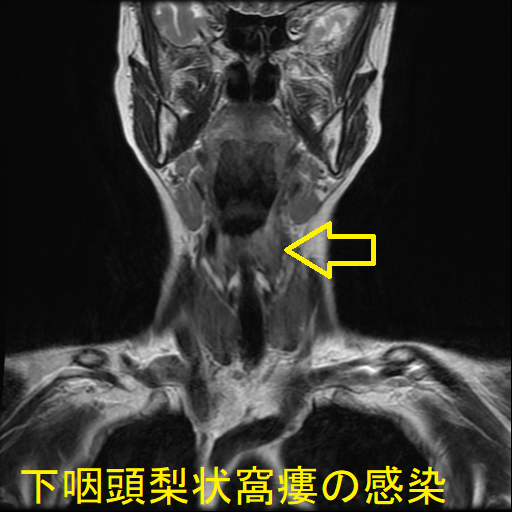

- 通常の造影頸部CTで、甲状腺外の膿瘍形成と、その範囲が明らかになります。

- 下咽頭部造影CTで、下咽頭梨状窩瘻を見つけます。

降下性壊死性縦隔炎とは、歯科治療・扁桃腺炎などによる頚部の深部感染症が、縦隔まで下りてくる病態。発熱・強烈な頚部痛があるものの喉頭ファイバーは異常なし。甲状腺周囲に膿瘍形成することも。亜急性甲状腺炎や急性化膿性甲状腺炎と鑑別[甲状腺超音波エコー検査にて否定]。MRI/CTにて診断可能。胸膜炎や膿胸も来す。敗血症による死亡率高く、早期に縦隔ドレナージ(排膿)。亜急性甲状腺炎と誤診し、ステロイド投与すれば敗血症が増悪。下咽頭梨状窩瘻が甲状腺内でなく、甲状腺周囲に開口している場合、急性化膿性甲状腺炎に至らない。

降下性壊死性縦隔炎とは、歯科治療・扁桃腺炎などによる頚部の深部感染症が、筋膜の間隙をつたい、縦隔まで下りてくる病態です[Surg Gynecol Obstet (1983) 157 : 545-552]。

急性化膿性甲状腺炎に至らない下咽頭梨状窩瘻の感染もあります。下咽頭梨状窩瘻が甲状腺内でなく、甲状腺周囲に開口している場合に起こります。